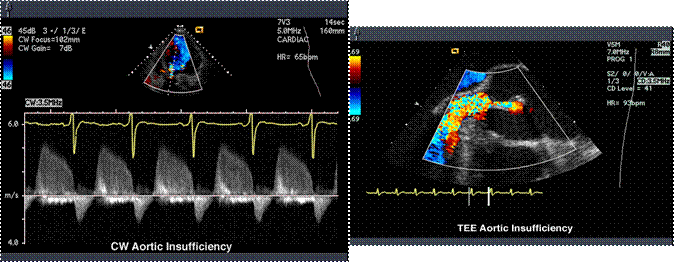

I.4.4. ECO Doppler - color fluxul turbulent in aorta ascendenta.

I.4.5. ECO Doppler PW = viteza si CW = gradientul presional.

M - mode: ecou de separare diastolic, flutter valvular mitral, > DTSVS > 55 mm

- flux turbulent (Doppler) cu velocitate crescuta,

- grade 1-4 in raport cu lungimea jetului.